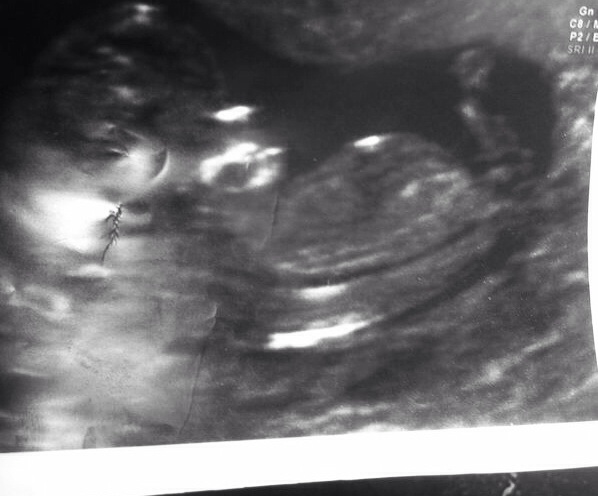

Hi, I have already posted this scan picture. But I am curious to know what part is the nub?

12.2 weeks. What part is the nub? Thank you x

It's the straight flat white line at the end of the torso...long and thin like a needle. Baby girl!

white line at the end of the body. looks girly!